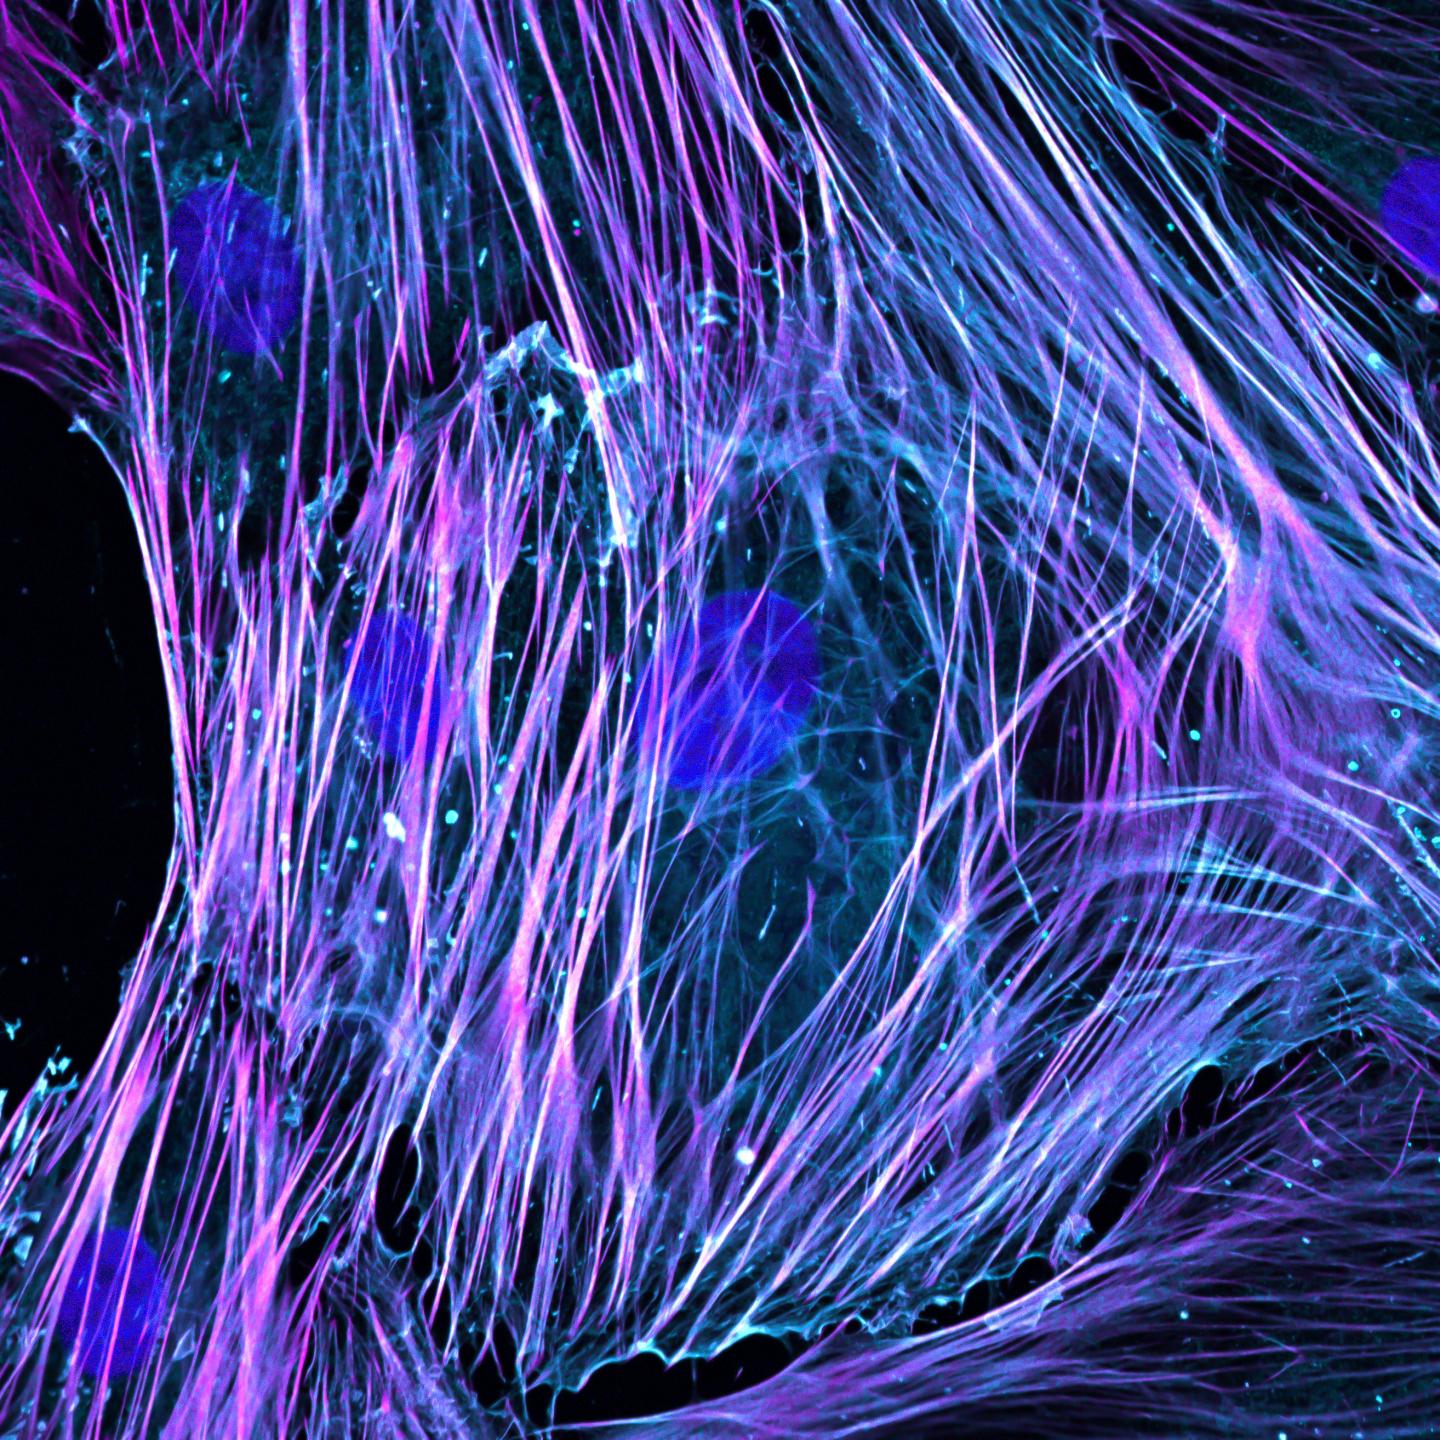

image: High-resolution fluorescence imaging of activated fibroblasts with immunostaining of nuclei (DAPI, blue), ACTA2 (purple) and F-actin (phalloidin, cyan) showing stress fibre formation.

Wang Mao, Duke-NUS Medical School